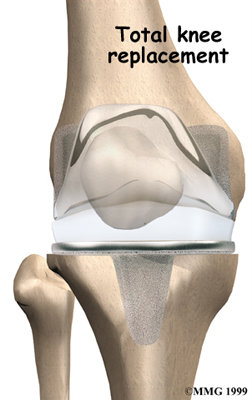

Artificial Knee Replacement

An artificial knee replacement is the ultimate solution for advanced knee OA.

Surgeons prefer not to put a new knee joint in patients younger than 60. This is because younger patients are generally more active and might put too much stress on the joint, causing it to loosen or even crack. A revision surgery to replace a damaged prosthesis is harder to do, has more possible complications, and is usually less successful than a first-time joint replacement surgery.

Related Document: FYZICAL Balcones Guide to Artificial Joint Replacement of the Knee